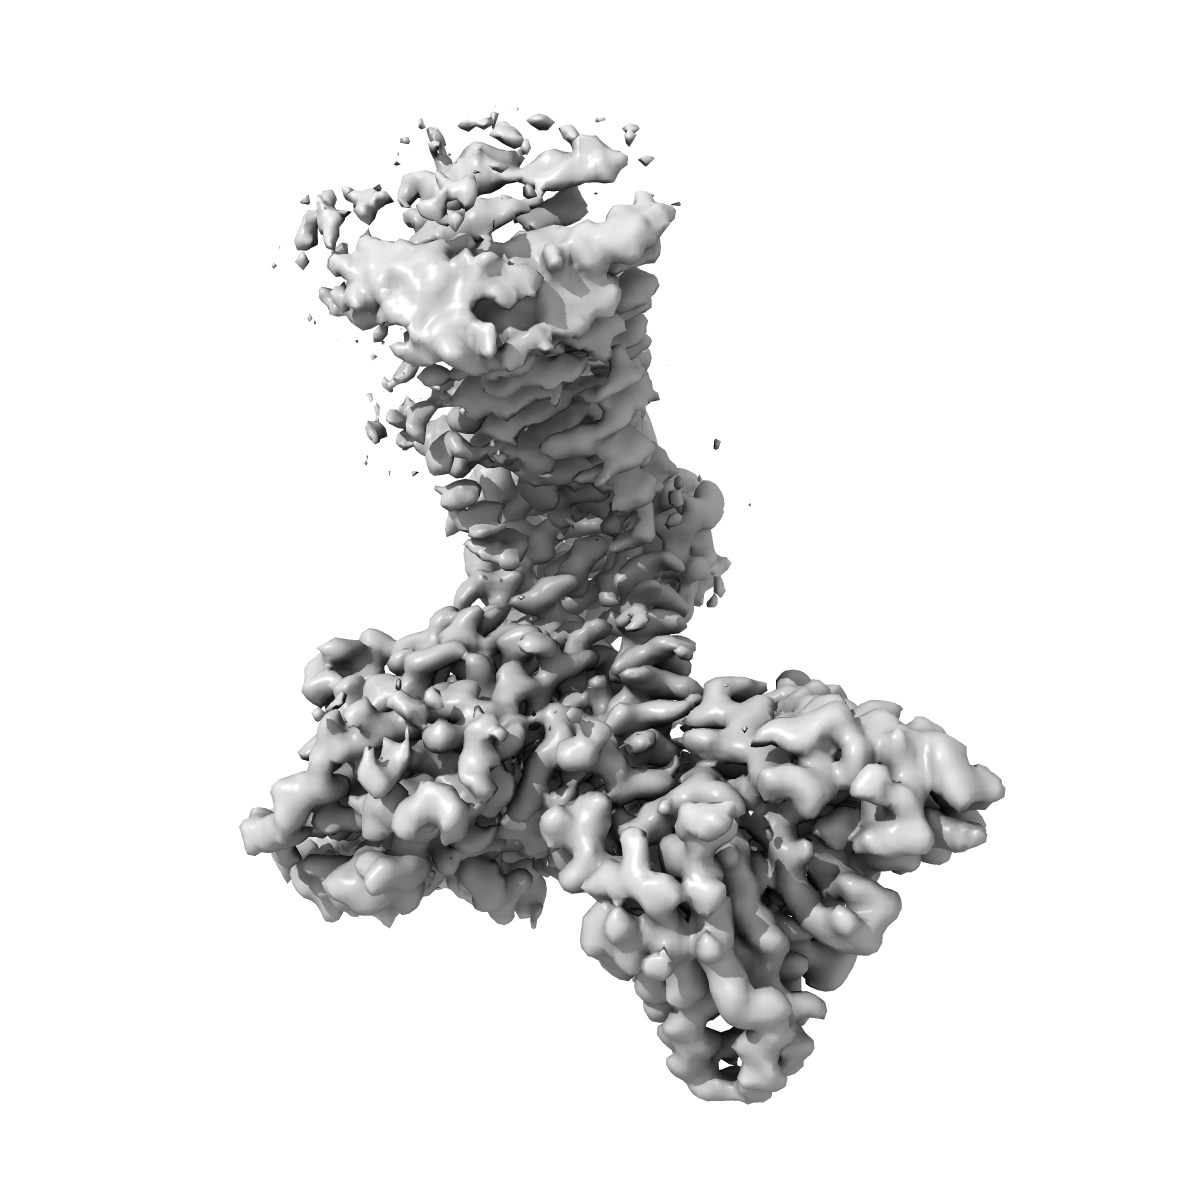

Cryo-EM structure of the TUG891 bound GPR120-Giq complex(mask on Giq-scFV16 complex)

Single-particle2.52 Å

Sample: Cryo-EM structure of the TUG891 bound GPR120-Giq complex

Unsaturated bond recognition leads to biased signal in a fatty acid receptor.

(2023) Science , 380 , eadd6220 - eadd6220